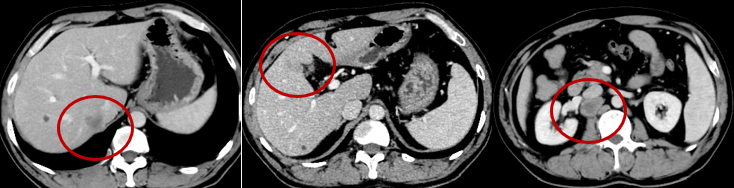

(2018-2-18)

(2018-7-15)

腹膜后淋巴结肿大,较前增大;

肝右叶腔静脉旁,胆囊窝旁低密度结节,较前新发,考虑转移。

肝脏MRI(2017.7.18):PD

肝内多发病变,结合病史,考虑转移灶。